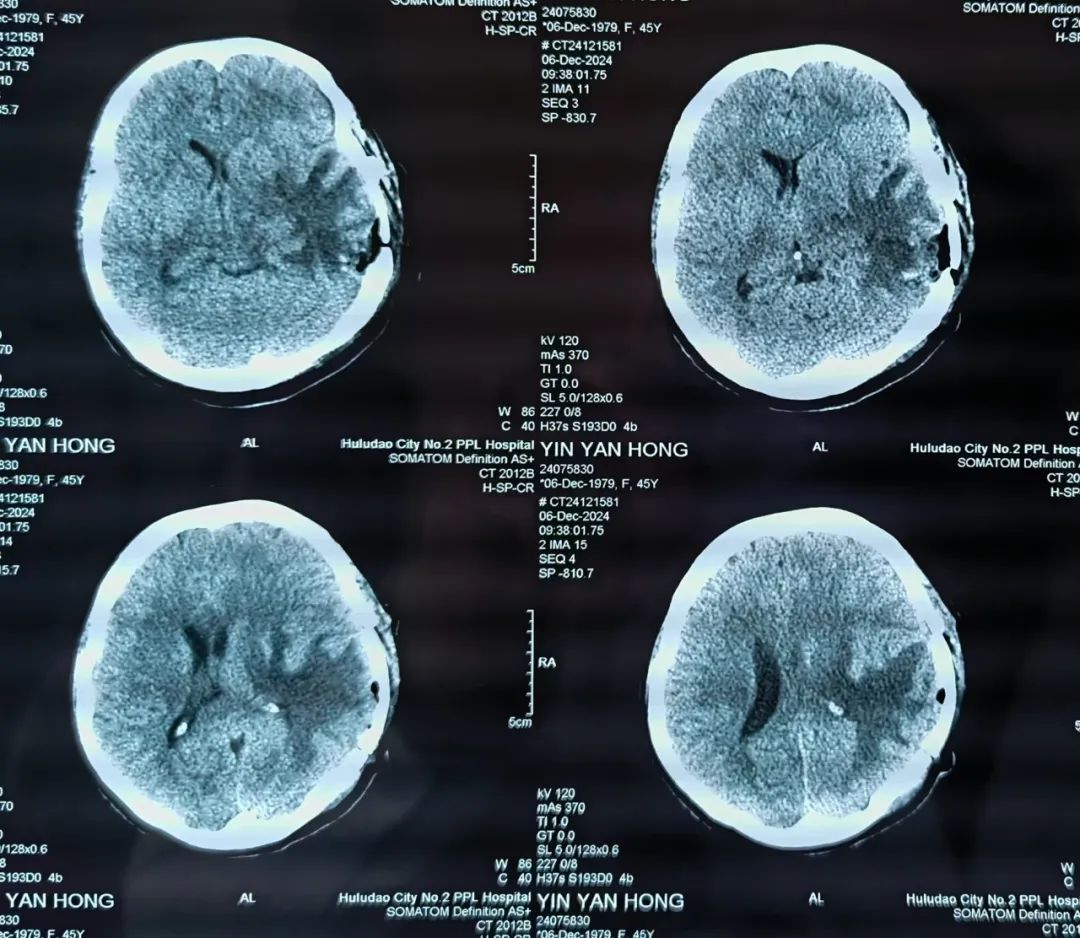

患者术后CT影像